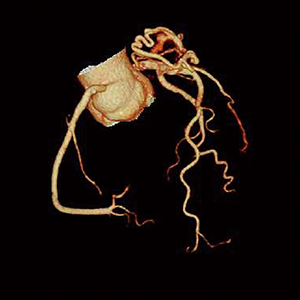

■症例1:冠動脈奇形症例

ボリューム撮影を行うことで、短時間かつ正確な画像を提供できる。